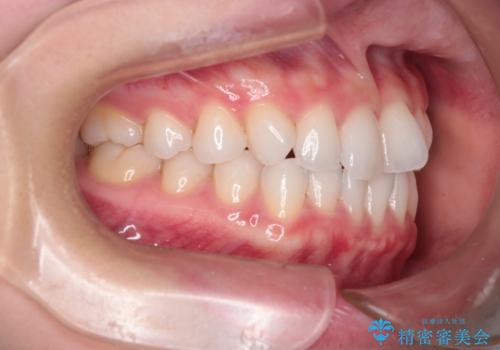

【インビザライン】前歯の凸凹をマウスピース矯正でなおしたい

- 前歯の凸凹を主訴に来院されました。

上の前歯は翼状捻転と呼ばれる状態でしたが、奥歯の遠心移動を行うことで配列スペースを確保することで綺麗に歯を並べることができました、

途中でインビザラインの使用時間が短くなってしまったため期間が予定より少し伸びましたが、1年半で満足いく結果となり患者様に喜んでいただけました。

下顎骨が右側に偏位していることにより下顎前歯の真ん中はずれています。